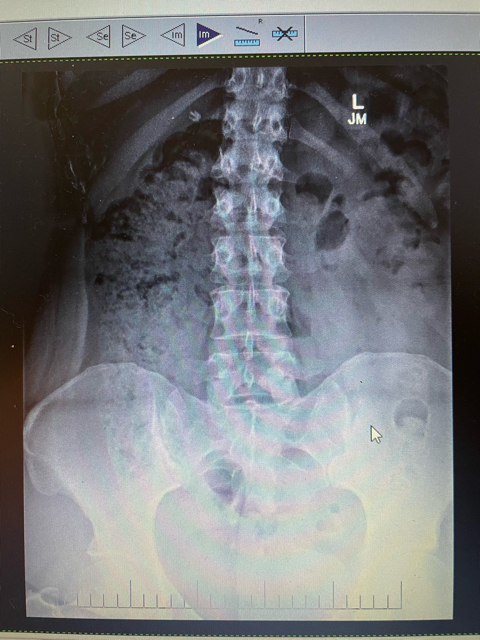

Got my X-rays done 🙏🏻

Any X-ray techs in the house? My doctor won’t be see me for a couple of weeks and I just got these today. I’ve been having insane lower back and hip pain for months. I’m just nervous not know anything and hurting my back more in that time.

To add: I’m not constipated at all. I go like clockwork every single morning, I take fiber supplements and I drink over 64 ounces of water a day minimum. I don’t have any abdominal pain. Just severe pain in the outside of my hips and my lower back.